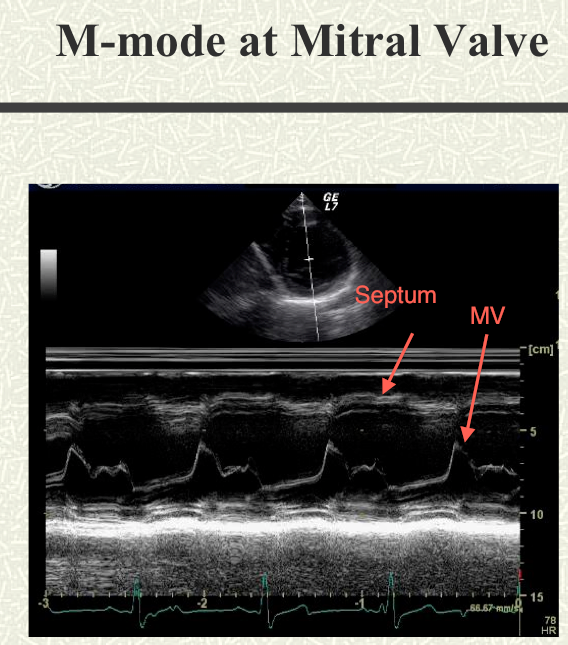

4. Slide your probe medially/laterally only if you need to in order to center the aortic and mitral valves on your screen.